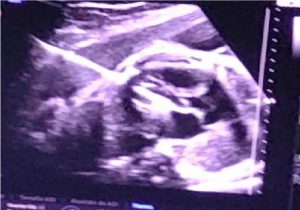

En un trabajo conjunto entre Fundación Hospitalaria y el Hospital Italiano de Buenos Aires, se realizó exitosamente el pasado 18 de diciembre una intervención cardíaca fetal en un feto de 32 semanas de gestación.

El procedimiento se realizó en un paciente sin cobertura proveniente de un hospital público, que ha sido derivado a la Fundación Hospitalaria para la realización de este tipo de prácticas quirúrgicas de alta complejidad y difícil resolución en una entidad pública. Su patología de base era una Estenosis Aórtica Crítica. Se trata de un procedimiento quirúrgico poco frecuente que se realiza en 15 centros en todo el mundo, y se han realizado ya 50 intervenciones en nuestro país.

Afirmó que lo más importante es el control y diagnóstico prenatal, porque «modifica la evolución de las cardiopatías», tanto para poder hacer una intervención intraútero o que cuando nazca, esté en un centro que tenga las capacidades que necesite el bebé. «Es importante que en cada ecografía se mire el funcionamiento del corazón del bebé».

Comentó también que lleva más tiempo organizarse que la intervención a sí misma, donde participaron 15 profesionales. «La herencia es multifactorial», aseguró Mercedes y agregó que no hay ningún alerta roja que te avise que pueda tener una cardiopatía, por eso es «muy importante que en la ecografía se mire el corazón al feto», ya que muchos pacientes no tienen antecedentes de problemas cardíacos.